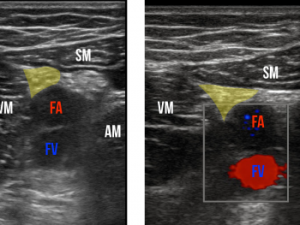

Figure 3: Sonographic view of the adductor canal. The saphenous nerve is highlighted.